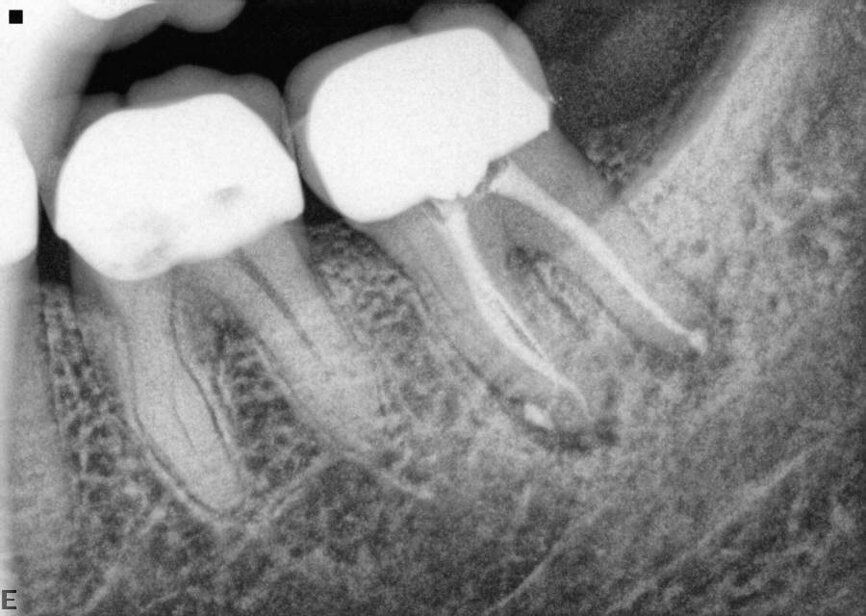

Fig. 13a: Case treated with Chlor-Xtra, SmearOFF with EndoUltra activation. Note the excellent cone fit and apical control of obturation. (Courtesy of Dr. Sam Alborz)

Fig. 13b: Case treated with Chlor-Xtra, SmearOFF with EndoUltra activation. Note the excellent cone fit and apical control of obturation. (Courtesy of Dr. Sam Alborz)